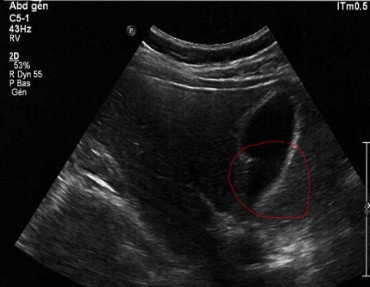

Examen échographique : ci dessous, je montre 2 images d'échographie avant et après nettoyage de la vésicule biliaire, confirmant qu'il y a eu expulsion des calculs biliaires grâce à la cure d'Andreas Moritz. Ces images sont tirées des témoignages de personnes ayant pratiqué cette cure.

- Vous faîtes une échographie de contrôle juste après la cure : la vésicule ne contient plus de calculs ou en contient moins. Le médecin en profite pour vérifier la paroi de la vésicule.